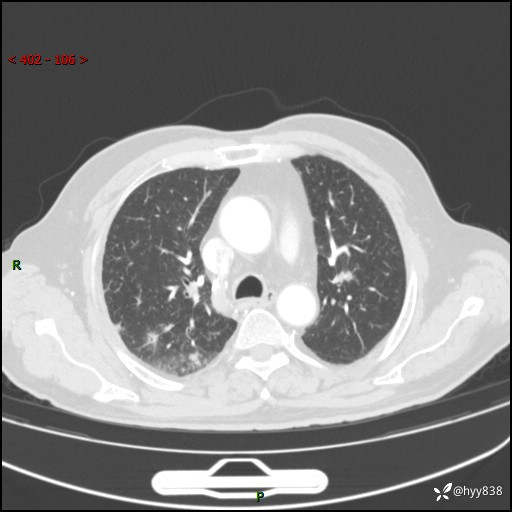

胸部CT复查(2024.7)

CT导向穿刺(靶点---2个结节)